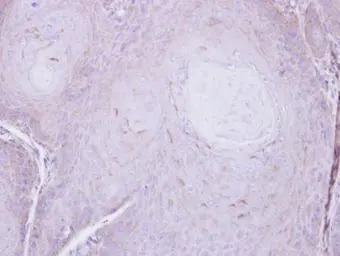

Immunohistochemical analysis of paraffin-embedded Cal27 xenograft , using C16orf62(GTX107271) antibody at 1:500 dilution.

Antigen Retrieval: Trilogy™ (EDTA based, pH 8.0) buffer, 15min